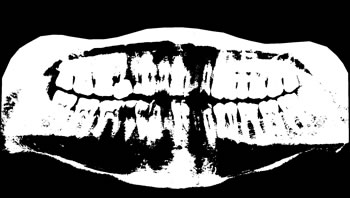

To thoroughly benchmark the methods studied here, the 1,500 images were distributed among 10 categories. The images were named, using whole numbers, in sequential order by category, aiming at not identifying the patients in the study. The process of categorizing the images was performed manually, selecting images individually, counting tooth by tooth, as well as verifying structural characteristics of the teeth. The images were classified according to the variety of structural characteristics of the teeth (see Table 5). Finally, the images were cut out to disregard non-relevant information (white border around the images and part of the spine) generated by the orthopantomograph device. After the clipping process, there was a change in the size of the images to 1991 ×\times 1127 pixels, but without affecting the objects of interest (teeth), as shown in Figure 2. The cropped images were saved on the new dimension to be used in the following stages, which will be presented in the next sections. Figure 3 shows an X-ray image corresponding to each of the categories of our data set.

Refer to caption

Figure 2: Example of the clipping and resizing of the data set images of the present work.